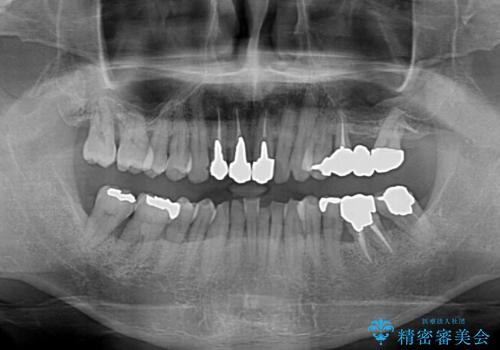

- 幼少期の薬剤の影響で歯が変色していていることを気にして来院された患者様です。

仕事も落ち着き、長年気にしていた前歯の色をきれいにしたいとのことでした。

上下ともに前歯のセラミッククラウンによる補綴治療を希望されていましたが、下顎前歯は叢生が強いため、補綴治療前に部分矯正を行って歯列を整えた上で、補綴治療を行うこととしました。

臼歯部には歯周ポケットのある箇所が散見されましたが、まずは前歯を治療したいとのことで、治療を進めました。

ディープバイトにより臼歯部に負担のかかる咬合であったので、補綴治療後には、矯正治療の後戻り防止もかねて、睡眠時にマウスピースを装着するように指示しました。